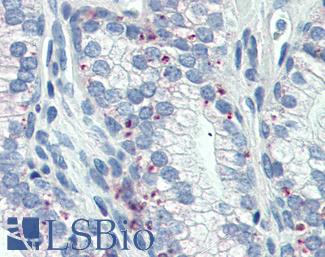

Anti-Smooth Muscle Actin antibody IHC of human prostate, smooth muscle. Immunohistochemistry of formalin-fixed, paraffin-embedded tissue after heat-induced antigen retrieval. Antibody LS-B7351 dilution 1:50.

Anti-Myosin, Smooth Muscle Heavy Chain antibody IHC of human prostate. Immunohistochemistry of formalin-fixed, paraffin-embedded tissue after heat-induced antigen retrieval. Antibody LS-B5148 concentration 20 ug/ml.